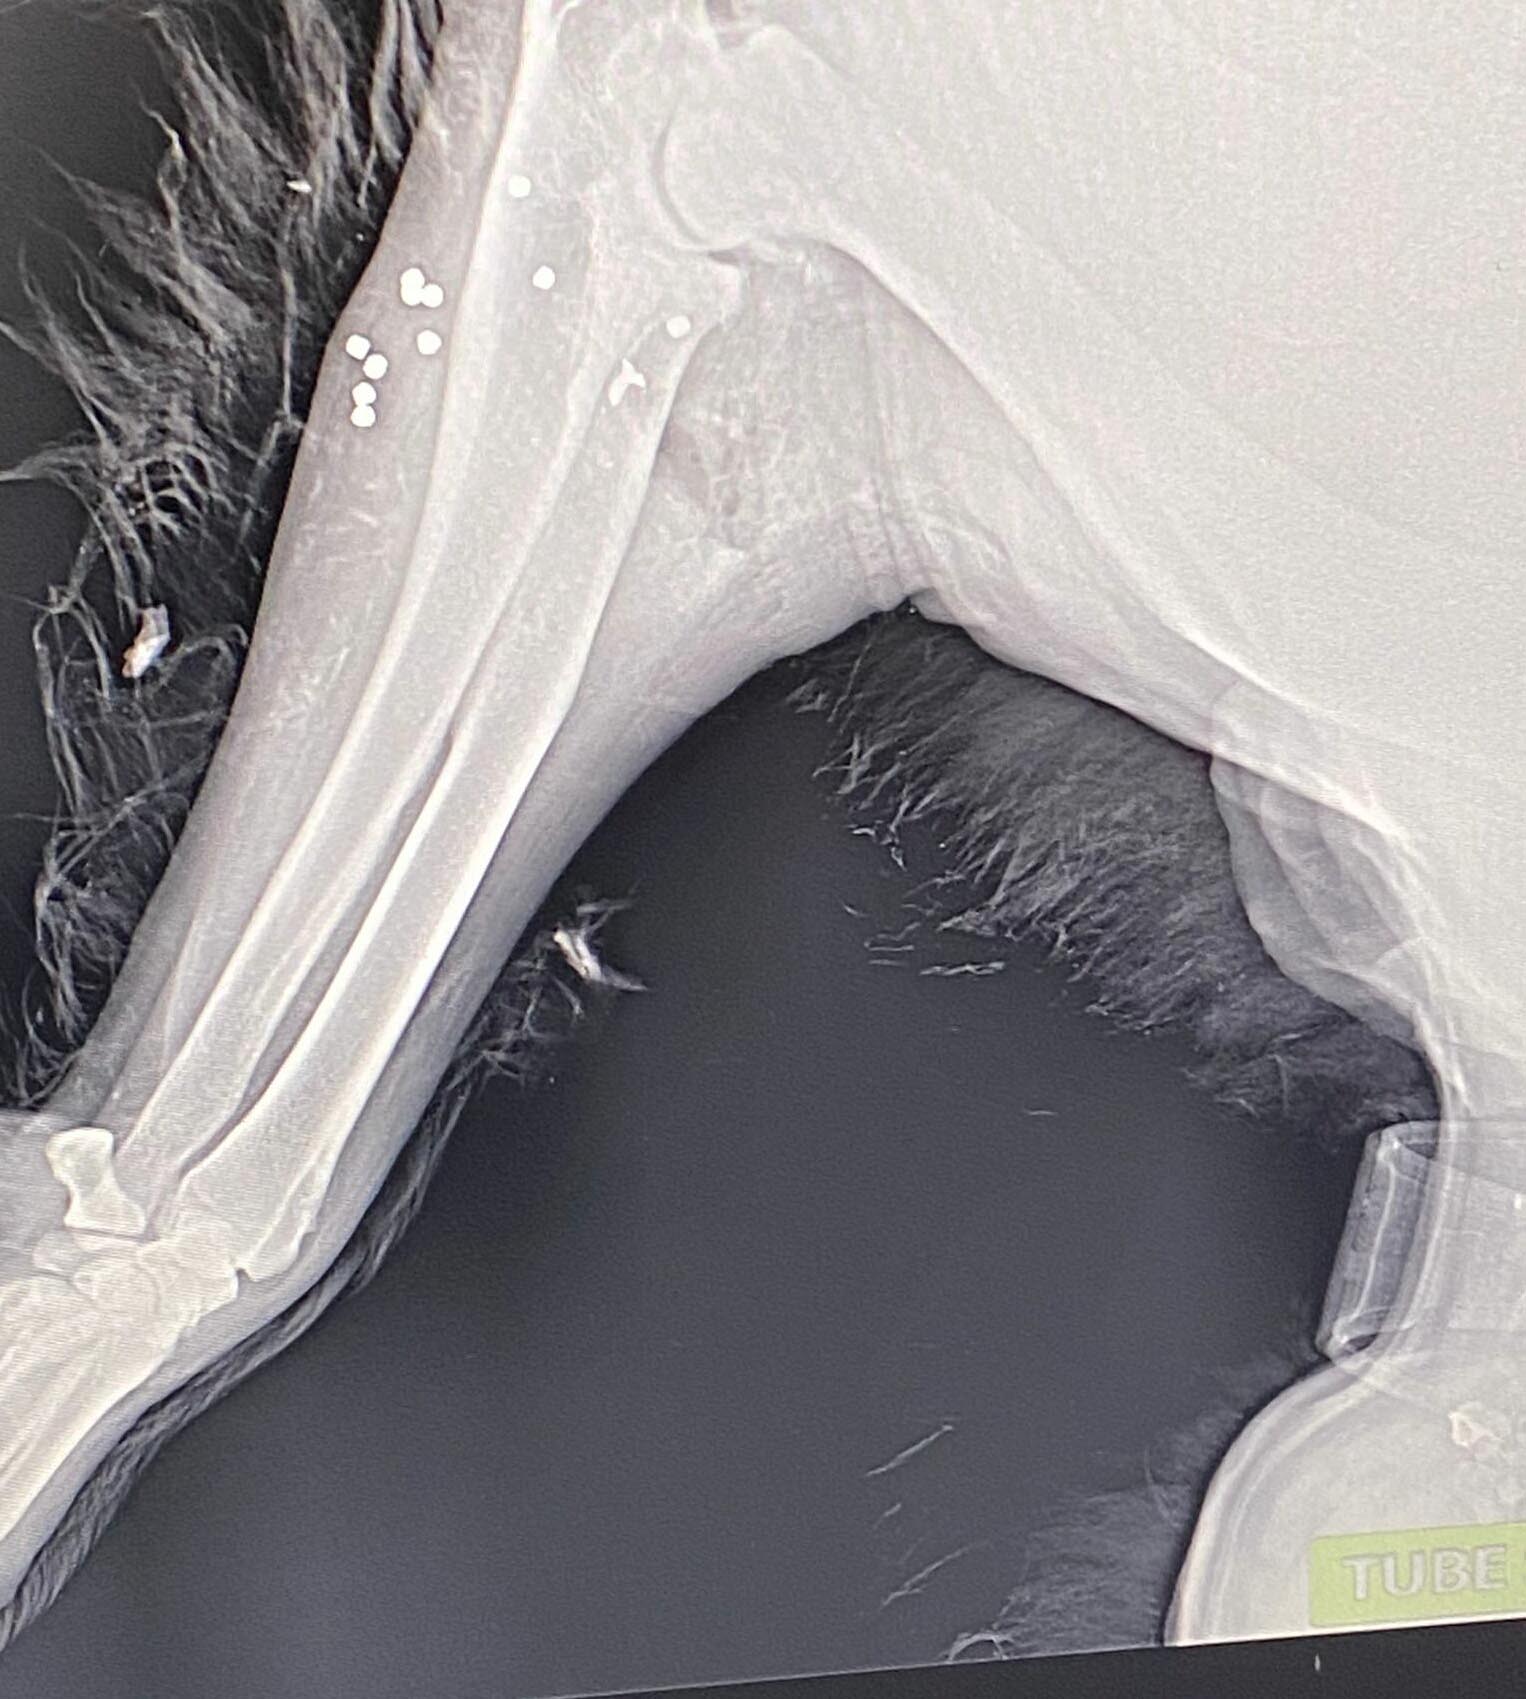

Bir süre sonra eve gelen Serhan Karadağ, kanlar içinde bulduğu köpeğini veterinere götürdü. Ameliyata alınan Leon'un vücudundaki saçmalar çıkarıldı. Karadağ, durumu jandarma ekiplerine bildirdi. Ekipler, şüphelinin bulunması için çalışma başlattı.

Köpeğinin tedavisinin sürdüğünü ancak henüz yürüyemediğini belirten Serkan Karadağ, "Şüpheli, beyaz bir otomobille gelip, Leon'u elindeki tasmayla yakalamaya çalışmış. Yakalayamayınca otomobilden aldığı pompalı tüfekle bir el ateş edip, yerden kartuşu da alarak kaçmış. Köpek eve sürünerek geliyor. Yerdeki kan izlerinden de anlaşılıyor. Leon'u veterinere götürdüm, ameliyat oldu. Vücudundan 5 saçma çıktı. Diğer saçmalar da içeride kaldı. Bu köpeğin başıboş değil. Tasmalı bir hayvanı tutup zincirleyemezsin. Sana saldırmıyor. Pompalı tüfekle vurmak ne demek? 'Benim değilsin, başkasının da olmazsın' demek mi istiyor? Sana zarar vermiyor, sen de sana zarar vermeyen bir hayvana zarar veremezsin. Canımızı yaktı, inşallah şüpheli bulunacak" dedi.